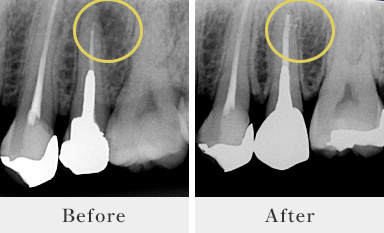

Before After

根管治療症例

「フィステル」と呼ばれる、歯根の先に溜まった膿の出口ができていました。根管治療により膿がなくなりフィステルが消失しました。

過去に根管治療を受け、再治療が必要になったケースです。治療に使用した「ファイル」が折れて根管の先に残留していたことが原因で感染を起こしていました。破折したファイルを取り除くのは技術が必要ですが、しっかりと取り除き根の先に溜まっていた膿がなくなりました。